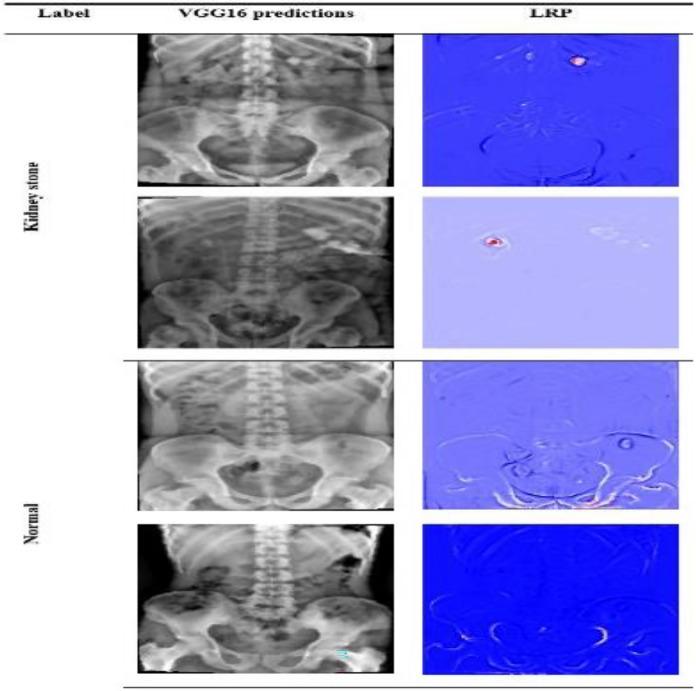

A kidney stone is a solid formation that can lead to kidney failure, severe pain, and reduced quality of life from urinary system blockages. While medical experts can interpret kidney-ureter-bladder (KUB) X-ray images, specific images pose challenges for human detection, requiring significant analysis time. Consequently, developing a detection system becomes crucial for accurately classifying KUB X-ray images. This article applies a transfer learning (TL) model with a pre-trained VGG16 empowered with explainable artificial intelligence (XAI) to establish a system that takes KUB X-ray images and accurately categorizes them as kidney stones or normal cases. The findings demonstrate that the model achieves a testing accuracy of 97.41% in identifying kidney stones or normal KUB X-rays in the dataset used. VGG16 model delivers highly accurate predictions but lacks fairness and explainability in their decision-making process. This study incorporates the Layer-Wise Relevance Propagation (LRP) technique, an explainable artificial intelligence (XAI) technique, to enhance the transparency and effectiveness of the model to address this concern. The XAI technique, specifically LRP, increases the model's fairness and transparency, facilitating human comprehension of the predictions. Consequently, XAI can play an important role in assisting doctors with the accurate identification of kidney stones, thereby facilitating the execution of effective treatment strategies.